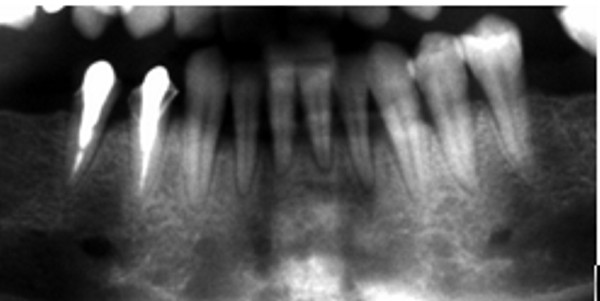

Porta radiografía panorámica (DIAPO 1), y teleradiografía , las que ofrecen una imagen francamente positiva para la instalación de Implante.

Actualmente enfermo periodontal, al que se le somete a raspaje y alisado radicular en toda la boca durante dos oportunidades con un año de separación, quien dada su condición de médico, es extremadamente colaboradora en su higiene, ya que suele acumular sarro duro dental con frecuencia.

Fumadora.

INICIAL

(A nivel periodóntico, endodóntico, A.T.M. y una oclusión absolutamente estable)

( REF.2) , abordamos la implantación inmediata, en lo que consideramos condiciones óptimas para la misma.